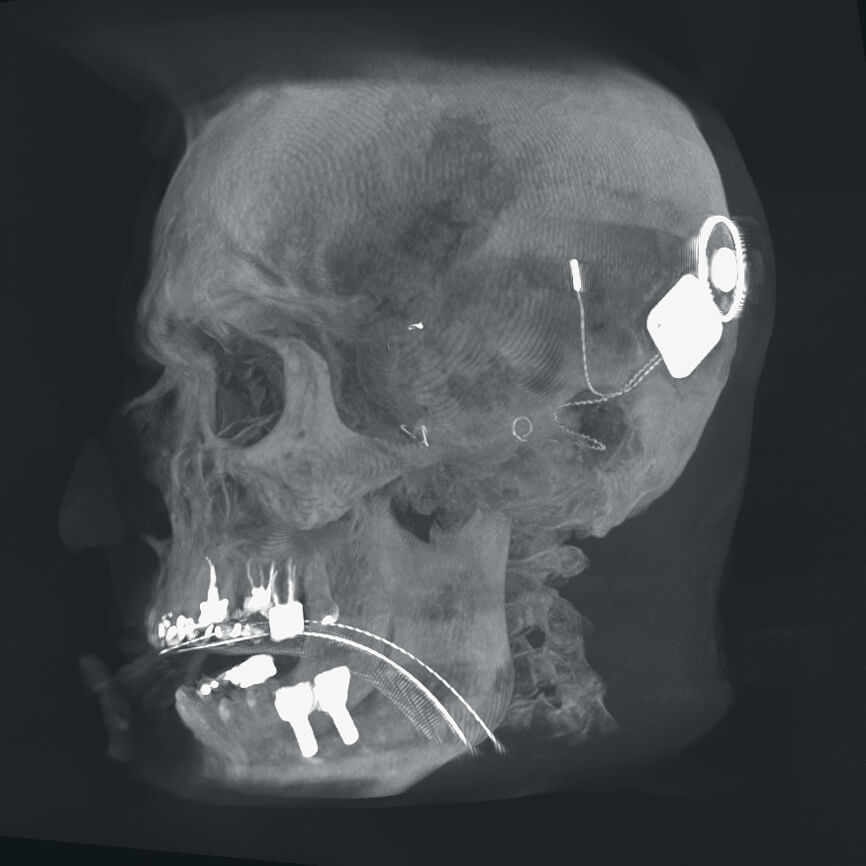

Синхронизация с системами стереотаксической навигации

Возможность оправки 3D изображений на стереотаксические системы Bainlab, Medtronic, Stryker для проведения хирургических вмешательств с использованием нейронавигации с минимальной погрешностью смещения.

Информативность и качество визуального контроля

Vision RFD 3D — первый передвижной рентгеновский аппарат, который обеспечивает изображения, ранее доступные только на стационарных системах. Плоскопанельный детектор формирует поле в 2,5 раза больше, чем усилитель рентгеновского изображения 9″. Увеличивается количество визуальной информации, постоянно доступной врачу на экране монитора с высоким разрешением.

Полное отсутствие искажений снимков в сочетании с высоким динамическим диапазоном широко востребованы как при сложных операциях в нейрохирургии, сосудистой хирургии, инвазивной радиологии, так и в гибридных областях применения, а также в ортопедии, травматологии. В сосудистой хирургии особенно важны высокий динамический диапазон и пространственное разрешение, обеспечивающие детальную визуализацию даже мельчайших сосудов. Специализированное программное обеспечение SmartVascular позволяет проводить настройку системы для васкулярных операций и сосудистой хирургии.

Точная визуализация анатомических деталей, мягких тканей и костных структур обеспечивается за счет светочувствительной матрицы 3kх3k пикселей с высоким динамическим диапазоном.